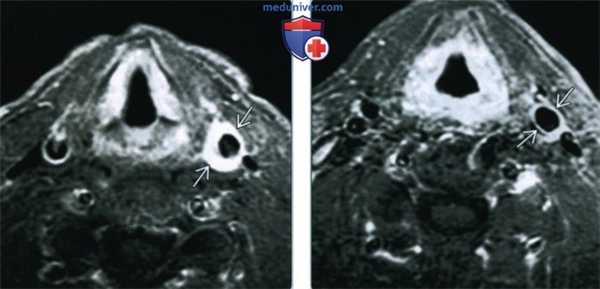

(Слева) МРТ Т1ВИ FS с КУ, аксиальный срез. Пациента беспокоит болезненность при пальпации области сонной артерии. Стенка общей сонной артерии утолщена, интенсивно накапливает контраст. Такие признаки характерны для каротидинии. Обратите внимание, что просвет сосуда не сужен.

(Справа) МРТ Т1ВИ FS с КУ, аксиальная проекция. Пациент с каротидинией после курса системных кортикостероидов. Отмечается небольшое остаточное утолщение стенки левой общей сонной артерии с накоплением в ней контрастного вещества.